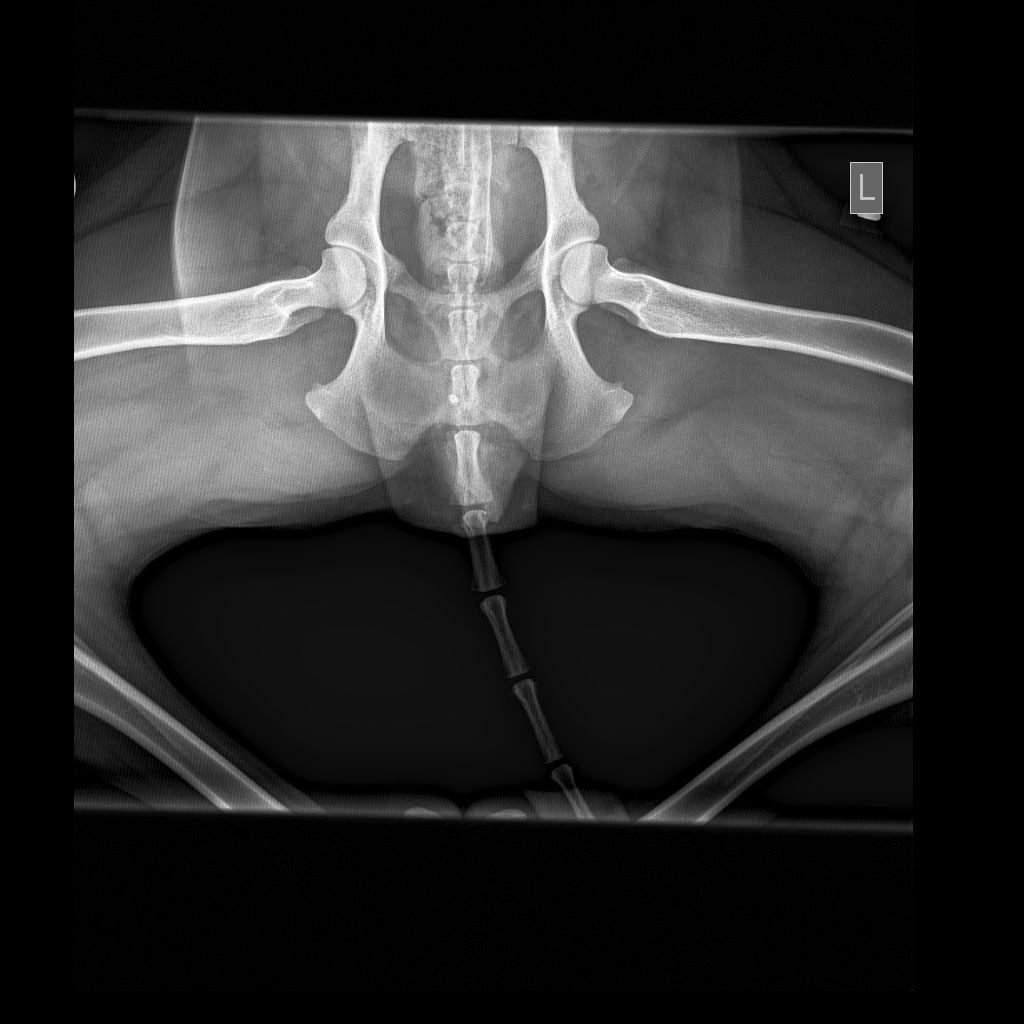

• HD Abklärungen

HD und ED Beurteilungen werden nach Wunsch des Besitzers oder nach Vorgaben der Rasseklubs jeweils von der HD-Kommission in Zürich oder Bern beurteilt. Für unsere deutschen Kunden ist auch ein Versand nach Deutschland möglich